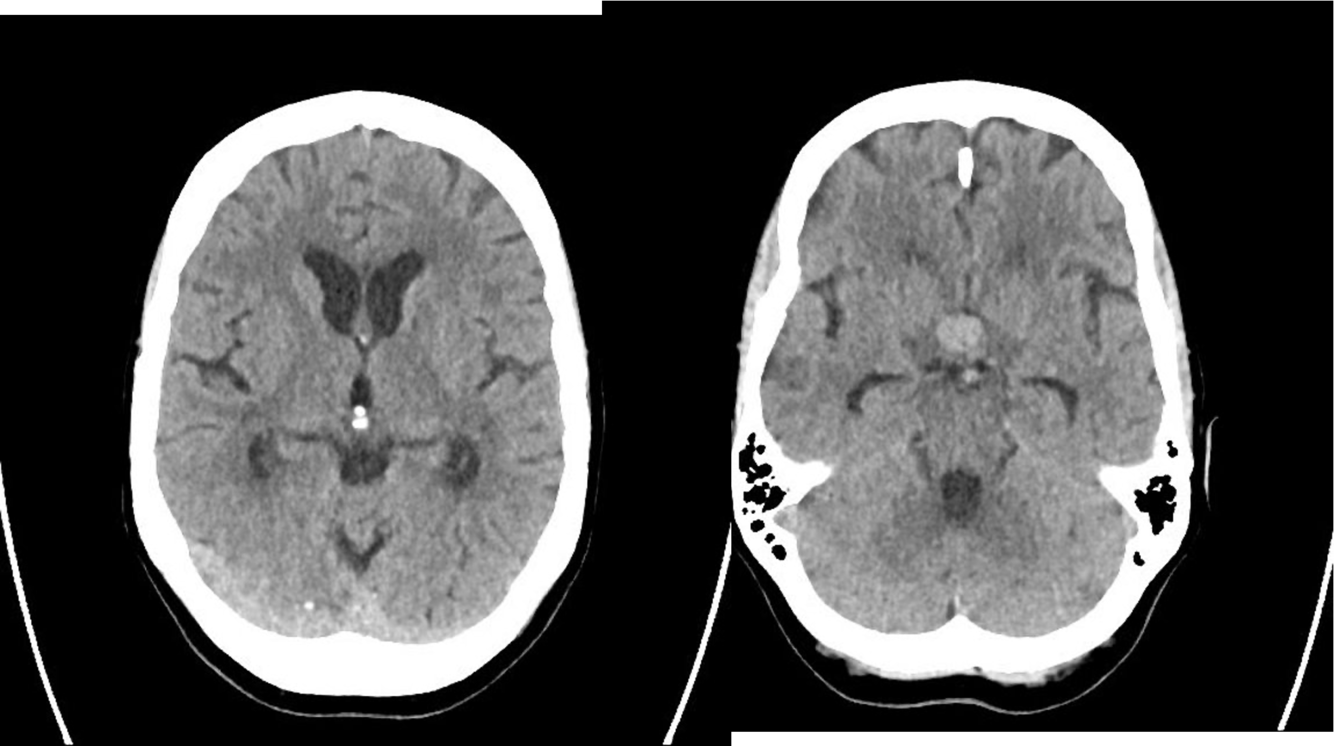

Marked obstructive hydrocephalus due to fourth ventricular outlet obstruction by fine septations

This case illustrates a classic Dandy Walker malformation with associated aqueduct stenosis and obstructive hydrocephalus, a common associated feature

(although not part of the Dandy walker triad: